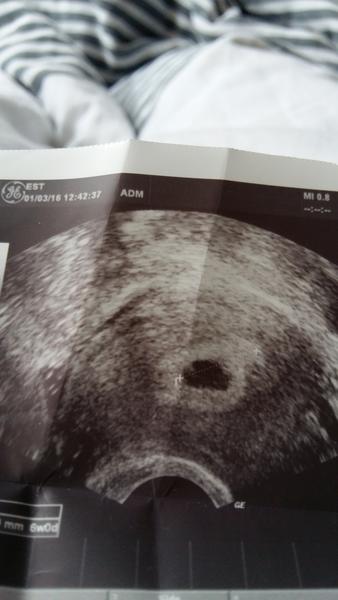

@svetluska17 byla jsem na kotrole 1.3.2016 a řekl že těhotenství odpovídá 4+6 že tam toho moc nevidí ale že gestační váček je 11mm dlouhý pošlu fotku jaký je na to názor jestli je to těhotenství či ne.

@puutalo to je mi moc líto jak jsi dopadla, určitě to bude vše dobré a budeš mít doma hromadu dětí, moc ti to přeji. Já byla včera v FN Motol Dr. mi udělal ultrazvuk řekl že kdyby tam něco bylo tak by to prý mělo srdíčko a bylo velké byla bych prý tak cca 10 týden od menstruace. Ale včera jak vytiskl obrázek tak jsem měla pocit že tam něco vidím, ano Dr. tvrdil že je tam vidět jen jakési plodové vejce ale už mi víc nevysvětlil a objednal mě na revizi.Taky jsem byla včera na nervy když jsem kolem sebe viděla hromadu ženských s bříškem a furt si říkám proč zrovna já . Ale doktor tvrdil že to tak příroda chtěla. 😢 😢